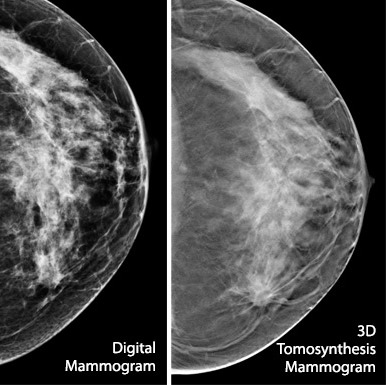

50,000 mammograms

20,000 tomosynthesis